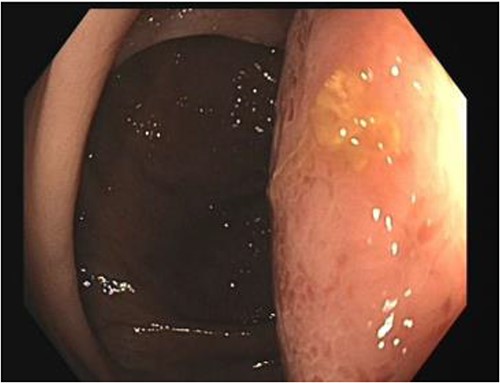

A number of differential diagnoses were considered including neoplastic and infectious pathologies such as latent TB, hydatid or amoebic cyst. A subsequent colonoscopy showed a submucosal semi-pedunculated lesion in the ascending colon measuring greater than 50 mm (Fig. 3). Biopsies were histologically nonspecific. As the patient was symptomatic of this lesion, and moreover as a malignant process could not be excluded, he proceeded with a surgical resection.